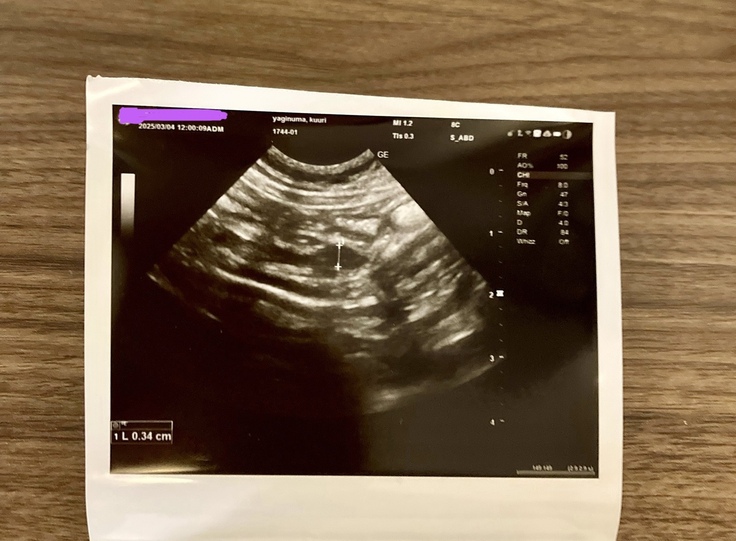

昨日病院に行って来ました。

数値がだいぶ正常値に近づいてきてました。

腸の近くのリンパの腫れだけが、全然小さくなってなくて心配です。

獣医師には、様子を見ましょうと言われました。

昨日はとても寒くて、病院で採血とエコーで